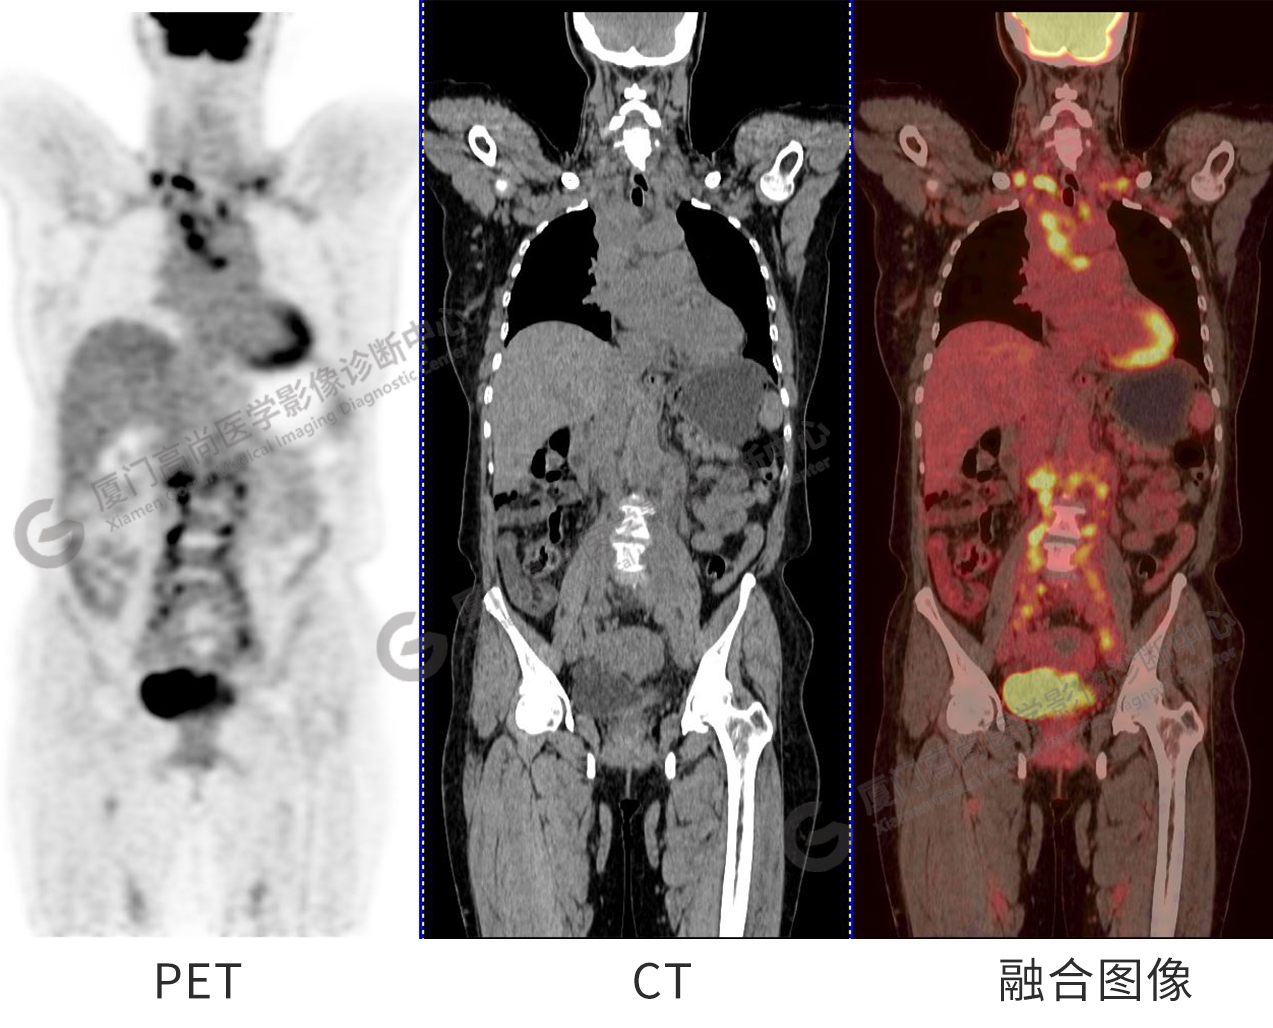

圖1:PET/CT全身圖像

圖2-9:雙側(cè)鎖骨區(qū)、縱隔、右側(cè)內(nèi)乳區(qū)、腸系膜緣、腹膜后、雙側(cè)髂血管旁及盆腔多發(fā)腫大淋巴結(jié)影,代謝不同程度增高,考慮為轉(zhuǎn)移。